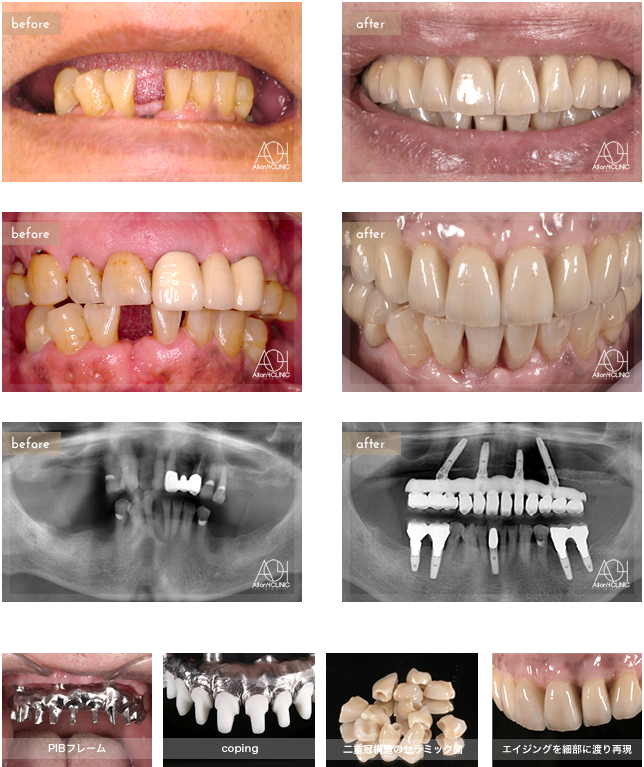

上顎All-on-4。上顎上部構造は二重冠構造(歯肉:アクリリックレジン/歯:セラミック)を採用。上顎の上部構造は、下顎に合わせエイジングを細部に渡り再現。